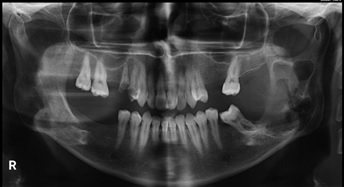

In intraoral examination, a sessile exophytic lesion with a smooth surface measuring 2 x 2.5 cm was observed on the posterior ridge of the left mandibular second molar, which was red in most areas with telangiectasia and normal in some areas. On buccal expansion palpation, bony hard was observed in the area of left mandibular second molar with a high probability of extension to the ramus, which also slightly involved the lingual side. However, the consistency of the ridge surface lesion (the mass resulting from bone perforation) was rubbery. Left mandibular second molar had anterior displacement and grade 1 looseness, but there was no tenderness or neurological symptoms. In examining the contact of the lesion with the tooth, the distolingual cusp of left maxillary tooth 7 and the maxillary ridge were in contact with the lesion, but no ulcer was formed (Figure 1).

Figure 1. Intraoral View: Exophytic lesion without base and smooth surface with red color and telangiectasia in the posterior ridge area of left mandibular second molar.